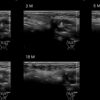

Draw in the image on the right where the fillers are located. To check if your answer is correct, please click on the secondary image.

Fillers